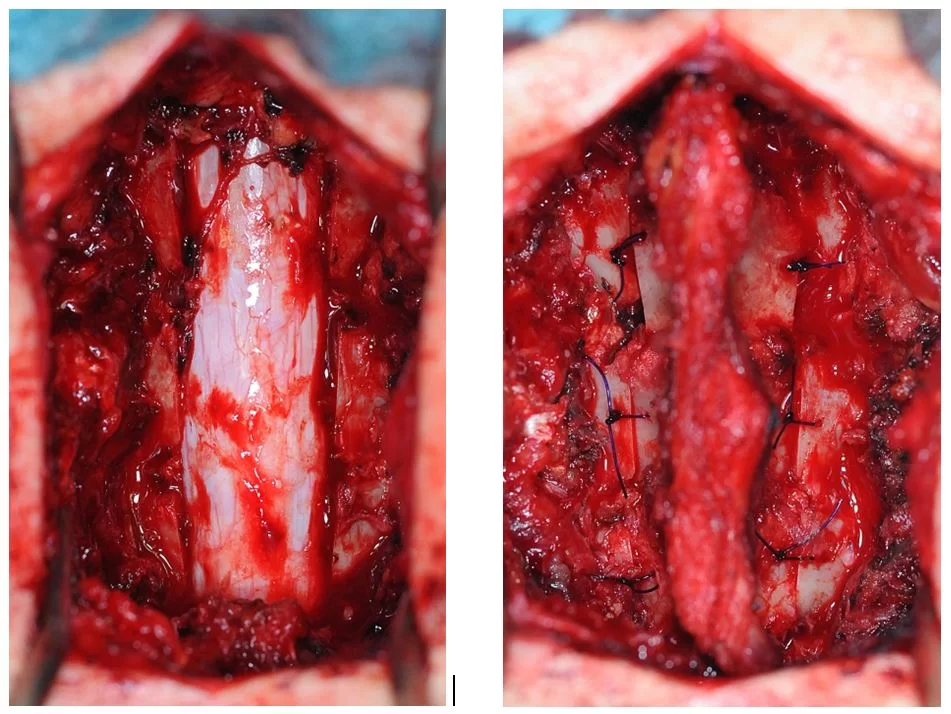

Οι ενδομυελικοί όγκοι αναπτύσσονται εντός του νωτιαίου μυελού (Εικόνα 1). Η συχνότητά τους σε σχέση με τους υπόλοιπους όγκους νωτιαίου μυελού είναι 5%. Τα αστροκυττώματα (στα παιδιά κυρίως) και τα επενδυμώματα (στους ενήλικες κυρίως) είναι οι συχνότεροι τύποι. Λιγότερο συχνοί τύποι είναι τα αιμαγγειοβλαστώματα, σηραγγώδη αγγειώματα και τα λιπώματα.

Χειρουργική Αντιμετώπιση: Οι ενδείξεις και ο τρόπος χειρουργικής αντιμετώπισης εξαρτώνται απολύτως από τον τύπο του όγκου. Πρωτοπαθείς (μη-μεταστατικοί) όγκοι των σπονδύλων χρειάζονται ριζική αφαίρεση με σπονδυλεκτομές. Σε περίπτωση μεταστάσεων συνήθως αρκεί η αποσυμπίεση των νευρικών δομών και η συμπληρωματική ακτινοβολία. Το αν υπάρχει ένδειξη για χειρουργείο σε ασθενή με μεταστατική νόσο σπονδυλικής στήλης είναι κάτι που πρέπει να συζητηθεί και να συναποφασιστεί με τους ογκολόγους. Για ενδοσκληρίδους όγκους όπως πχ. μηνιγγιώματα ή νευρινώματα, καθώς επίσης για ενδομυελικούς όγκους (πχ. αστροκυττώματα ή επενδυμώματα) η θεραπεία είναι η ολική χειρουργική αφαίρεση. Συνήθως χρησιμοποιούνται ελάχιστα επεμβατικές μέθοδοι ενώ αποφεύγεται η καταστροφή των υγιών ιστών και δομών της σπονδυλικής στήλης (Εικόνα 3). Μερικοί όγκοι, όπως πχ. το λίπωμα νωτιαίου μυελού, αφαιρούνται ιδιαίτερα αποτελεσματικά με τη χρήση λέιζερ (laser) (Εικόνα 4).